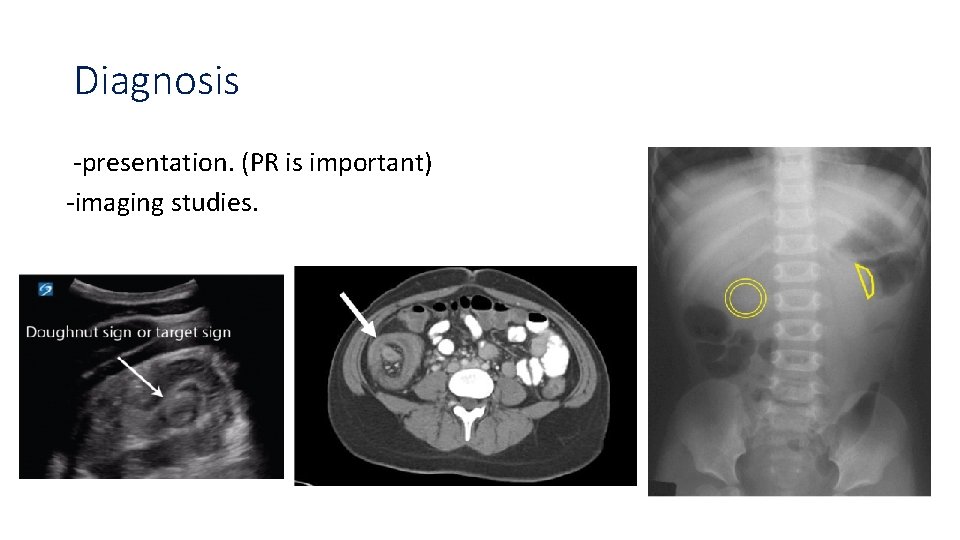

Case 4 8 month old infant, presented with rectal bleeding, greenish vomiting, with crying and irritability, on examination, there was a palpable mass in the RUQ. -what’s the most likely diagnosis? Intussusception. -Name of this stool? Red currant jelly stool. -What is the cause of it ? Mucus and blood. -what is sign of dance?

Red currant jelly stool

Classification -primary. -secondary (leading point). Anatomical classification: Ileocolic (77%). Ileoileocolic. Ileoileal. Etc.

Diagnosis -presentation. (PR is important) -imaging studies.

Contrast studies

Management Non operative management : Pneumatic or hydrostatic reduction under fluoroscopic or US guidance. If : failed manual method, complicated and atypical age of presentation , surgery is indicated.